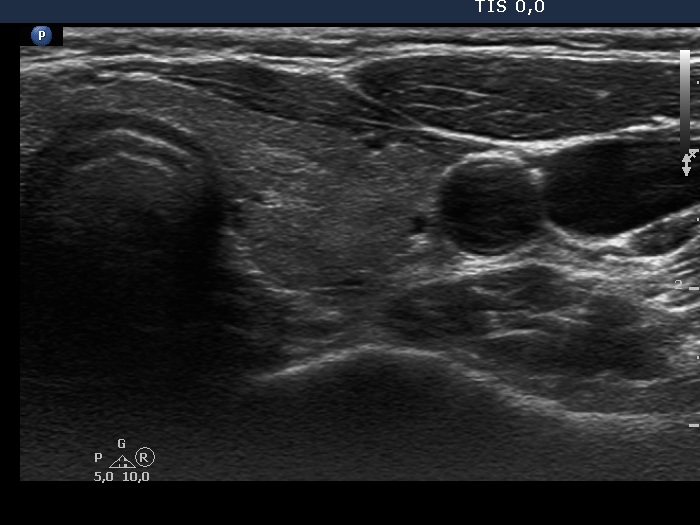

Right lobe, longitudinal scan

Left lobe, transverse scan. This lobe is also minimally hypoechogenic.